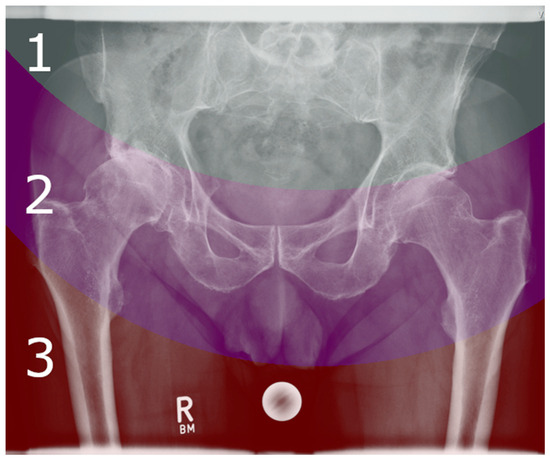

2.3. X-ray Grading